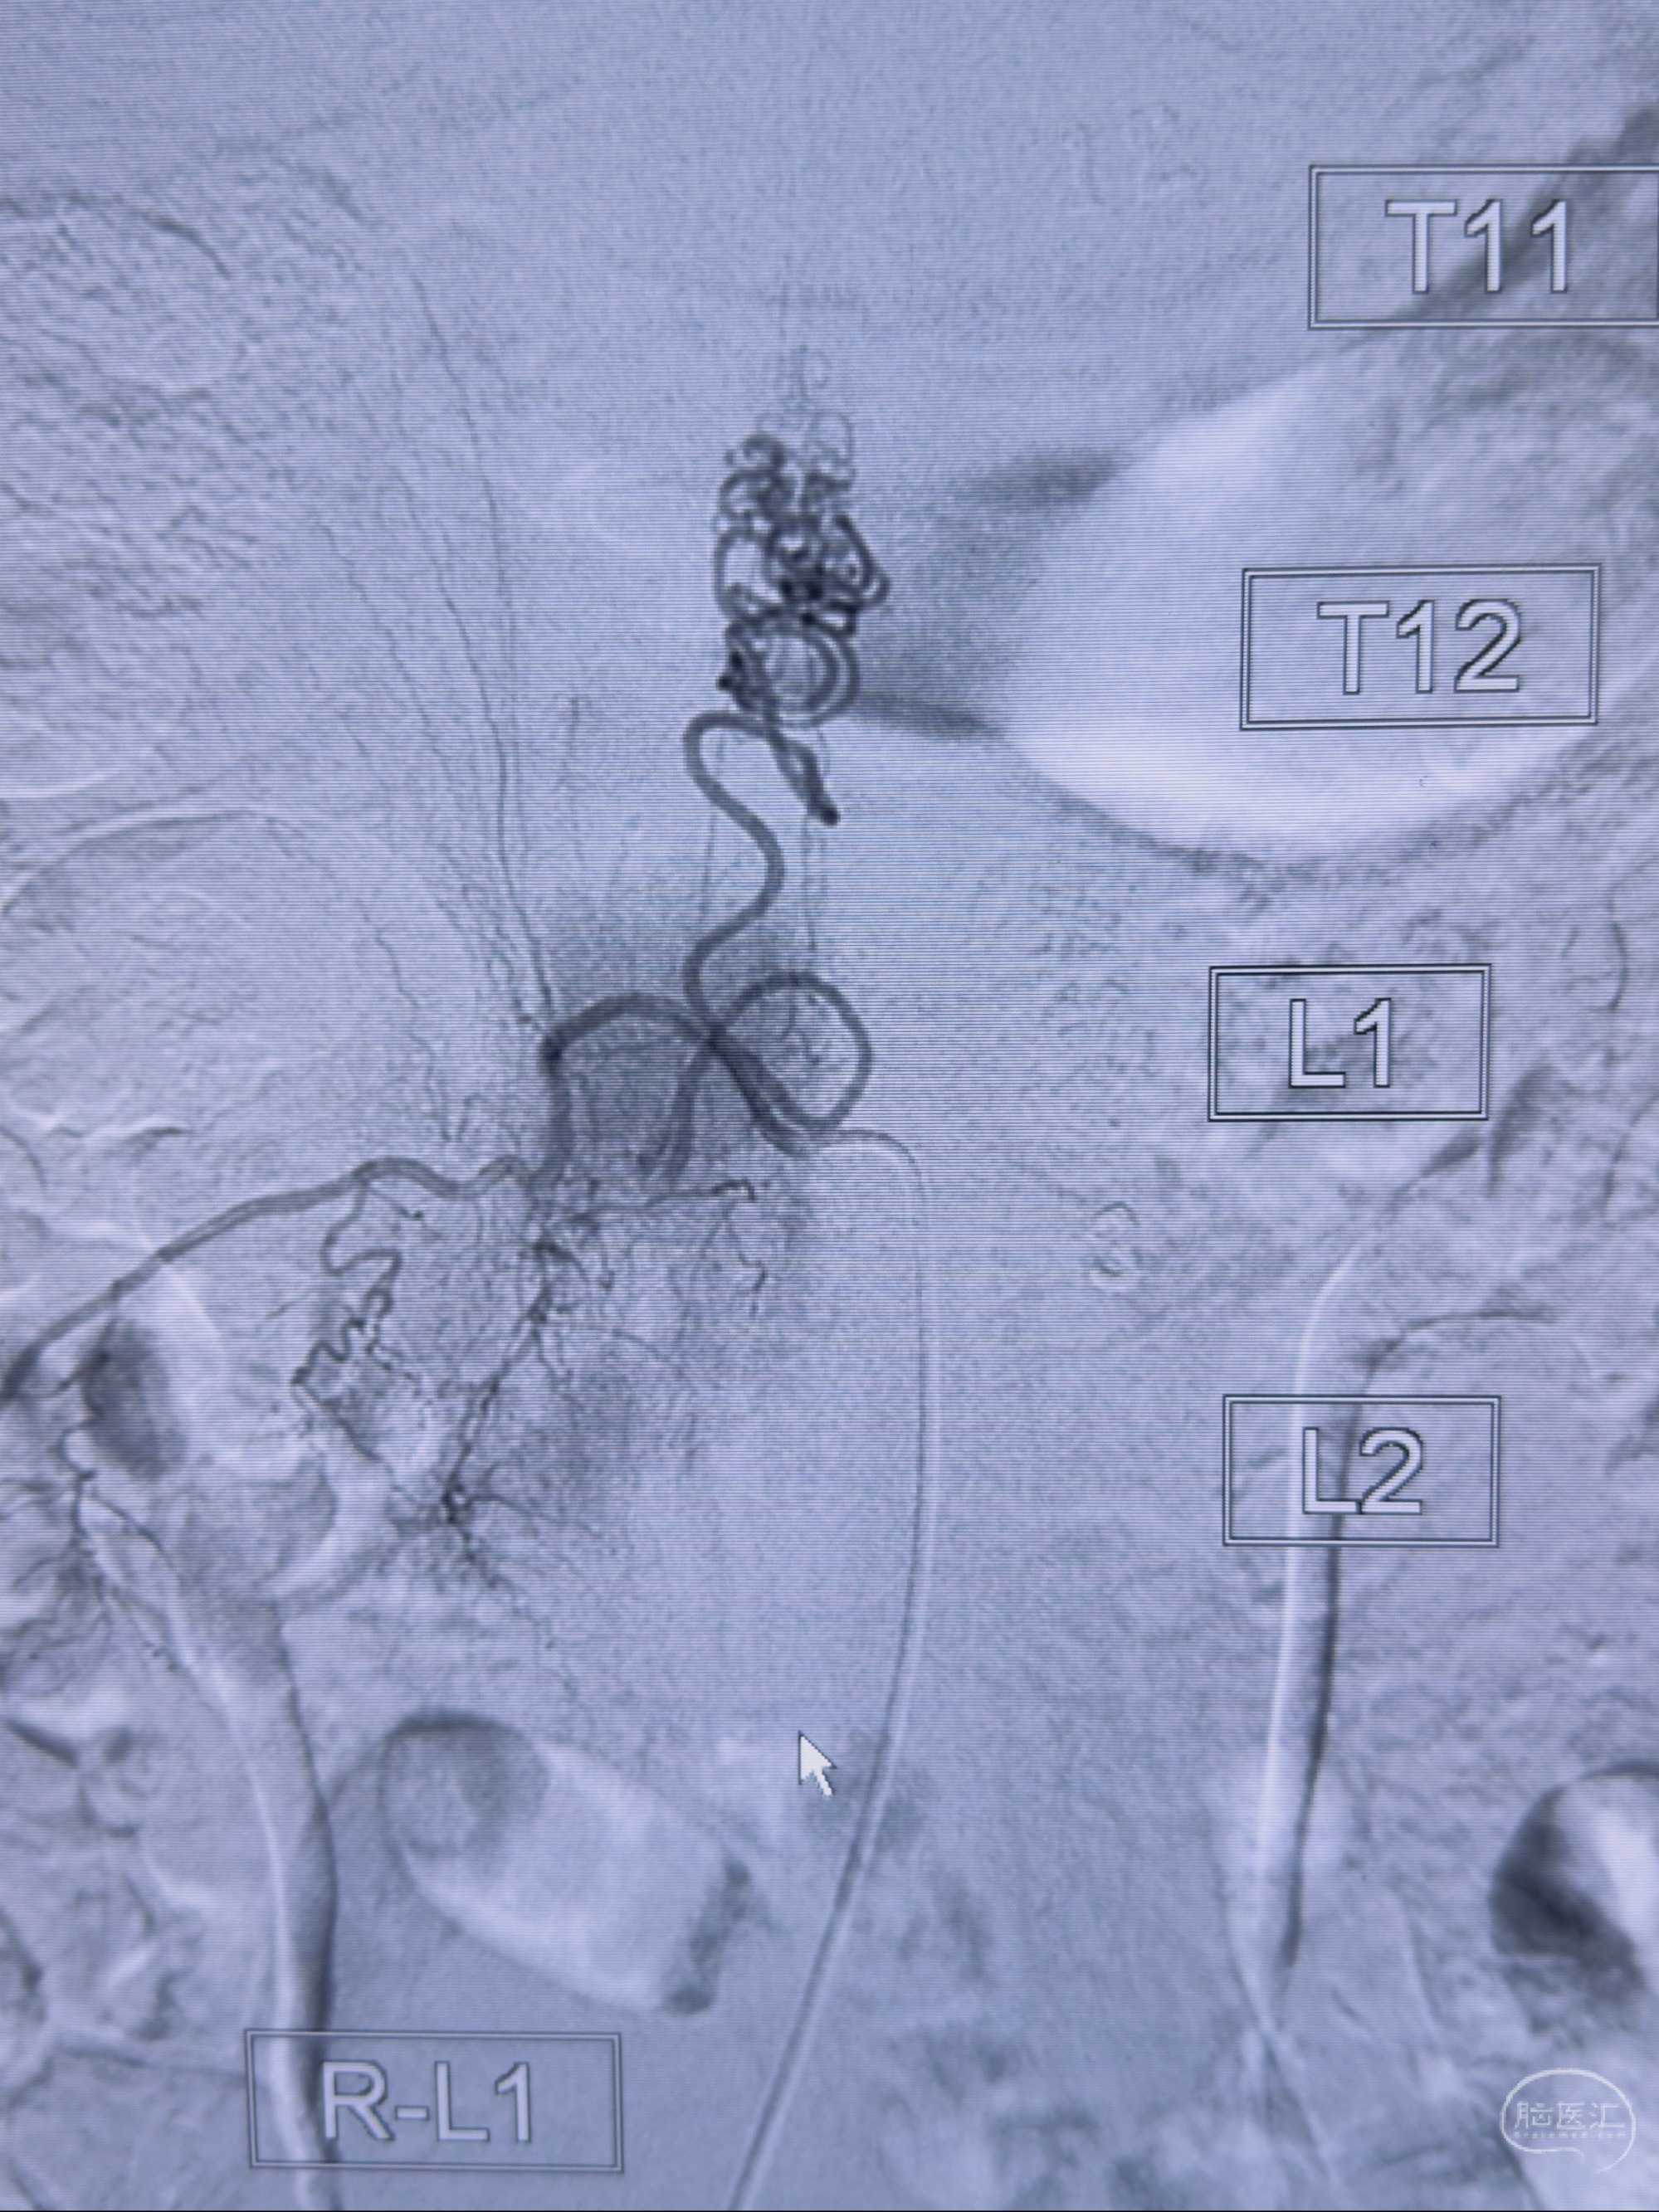

2023-10-13DSA:右侧L1水平硬脊膜动静脉瘘,供血动脉为右侧L1,附近动脉未见明确吻合供血,供血动脉处可见脊髓前动脉发出

治疗建议:

1.建议外科手术,已行美兰定位c